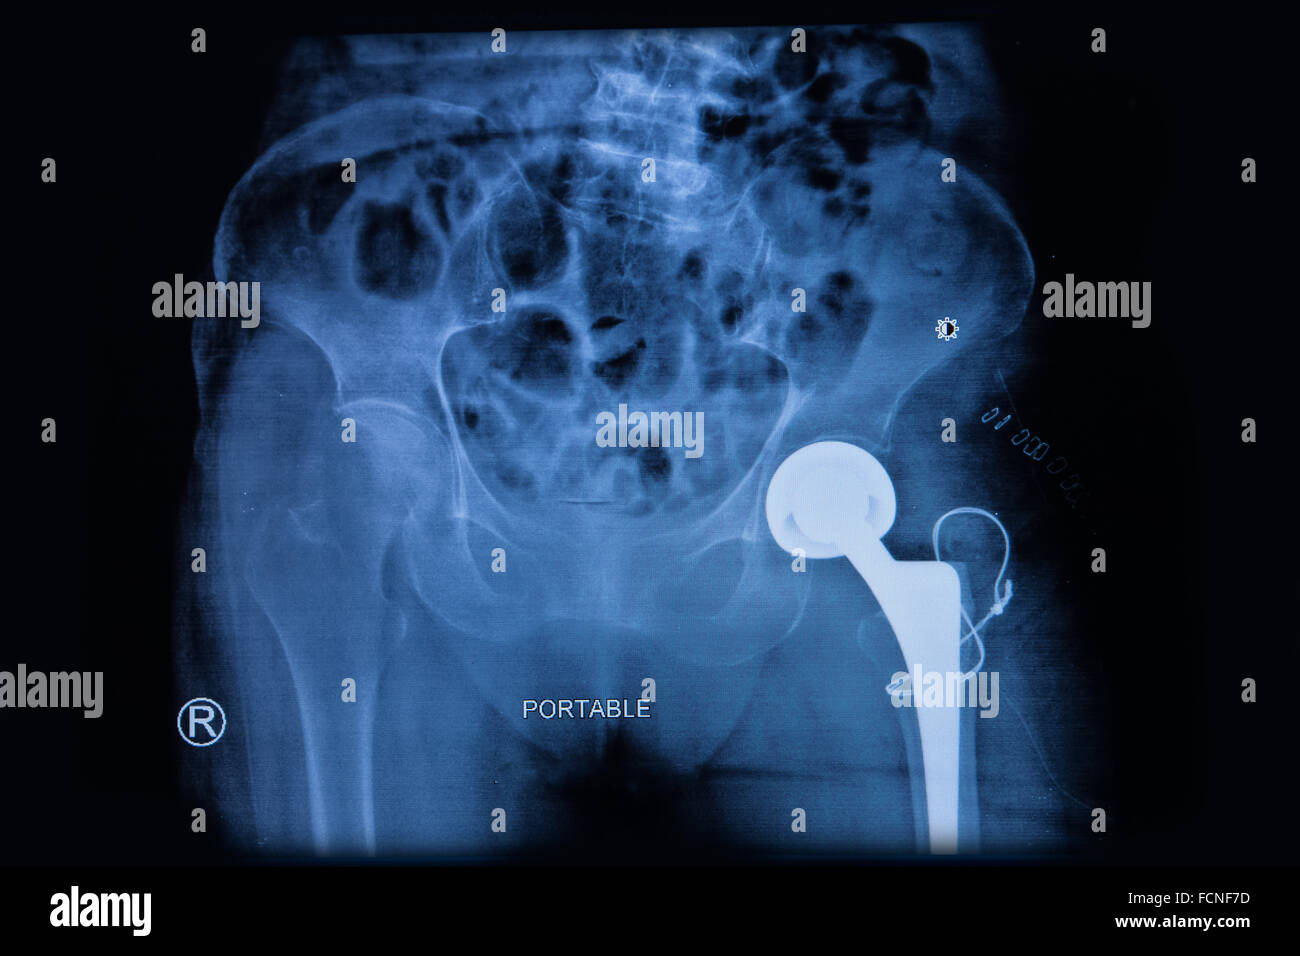

From www.alamy.com

Total hip replacement hires stock photography and images Alamy Hip Surgery For Elderly the choice between hemiarthroplasty and total hip arthroplasty requires a good estimate of the patient’s life. Research shows that hip fracture patients do better when surgery is performed within 24 hours of the injury. Now, experts from the american geriatrics society explain the true toll. The average age of hip surgery patients in the study was. hip fractures. Hip Surgery For Elderly.